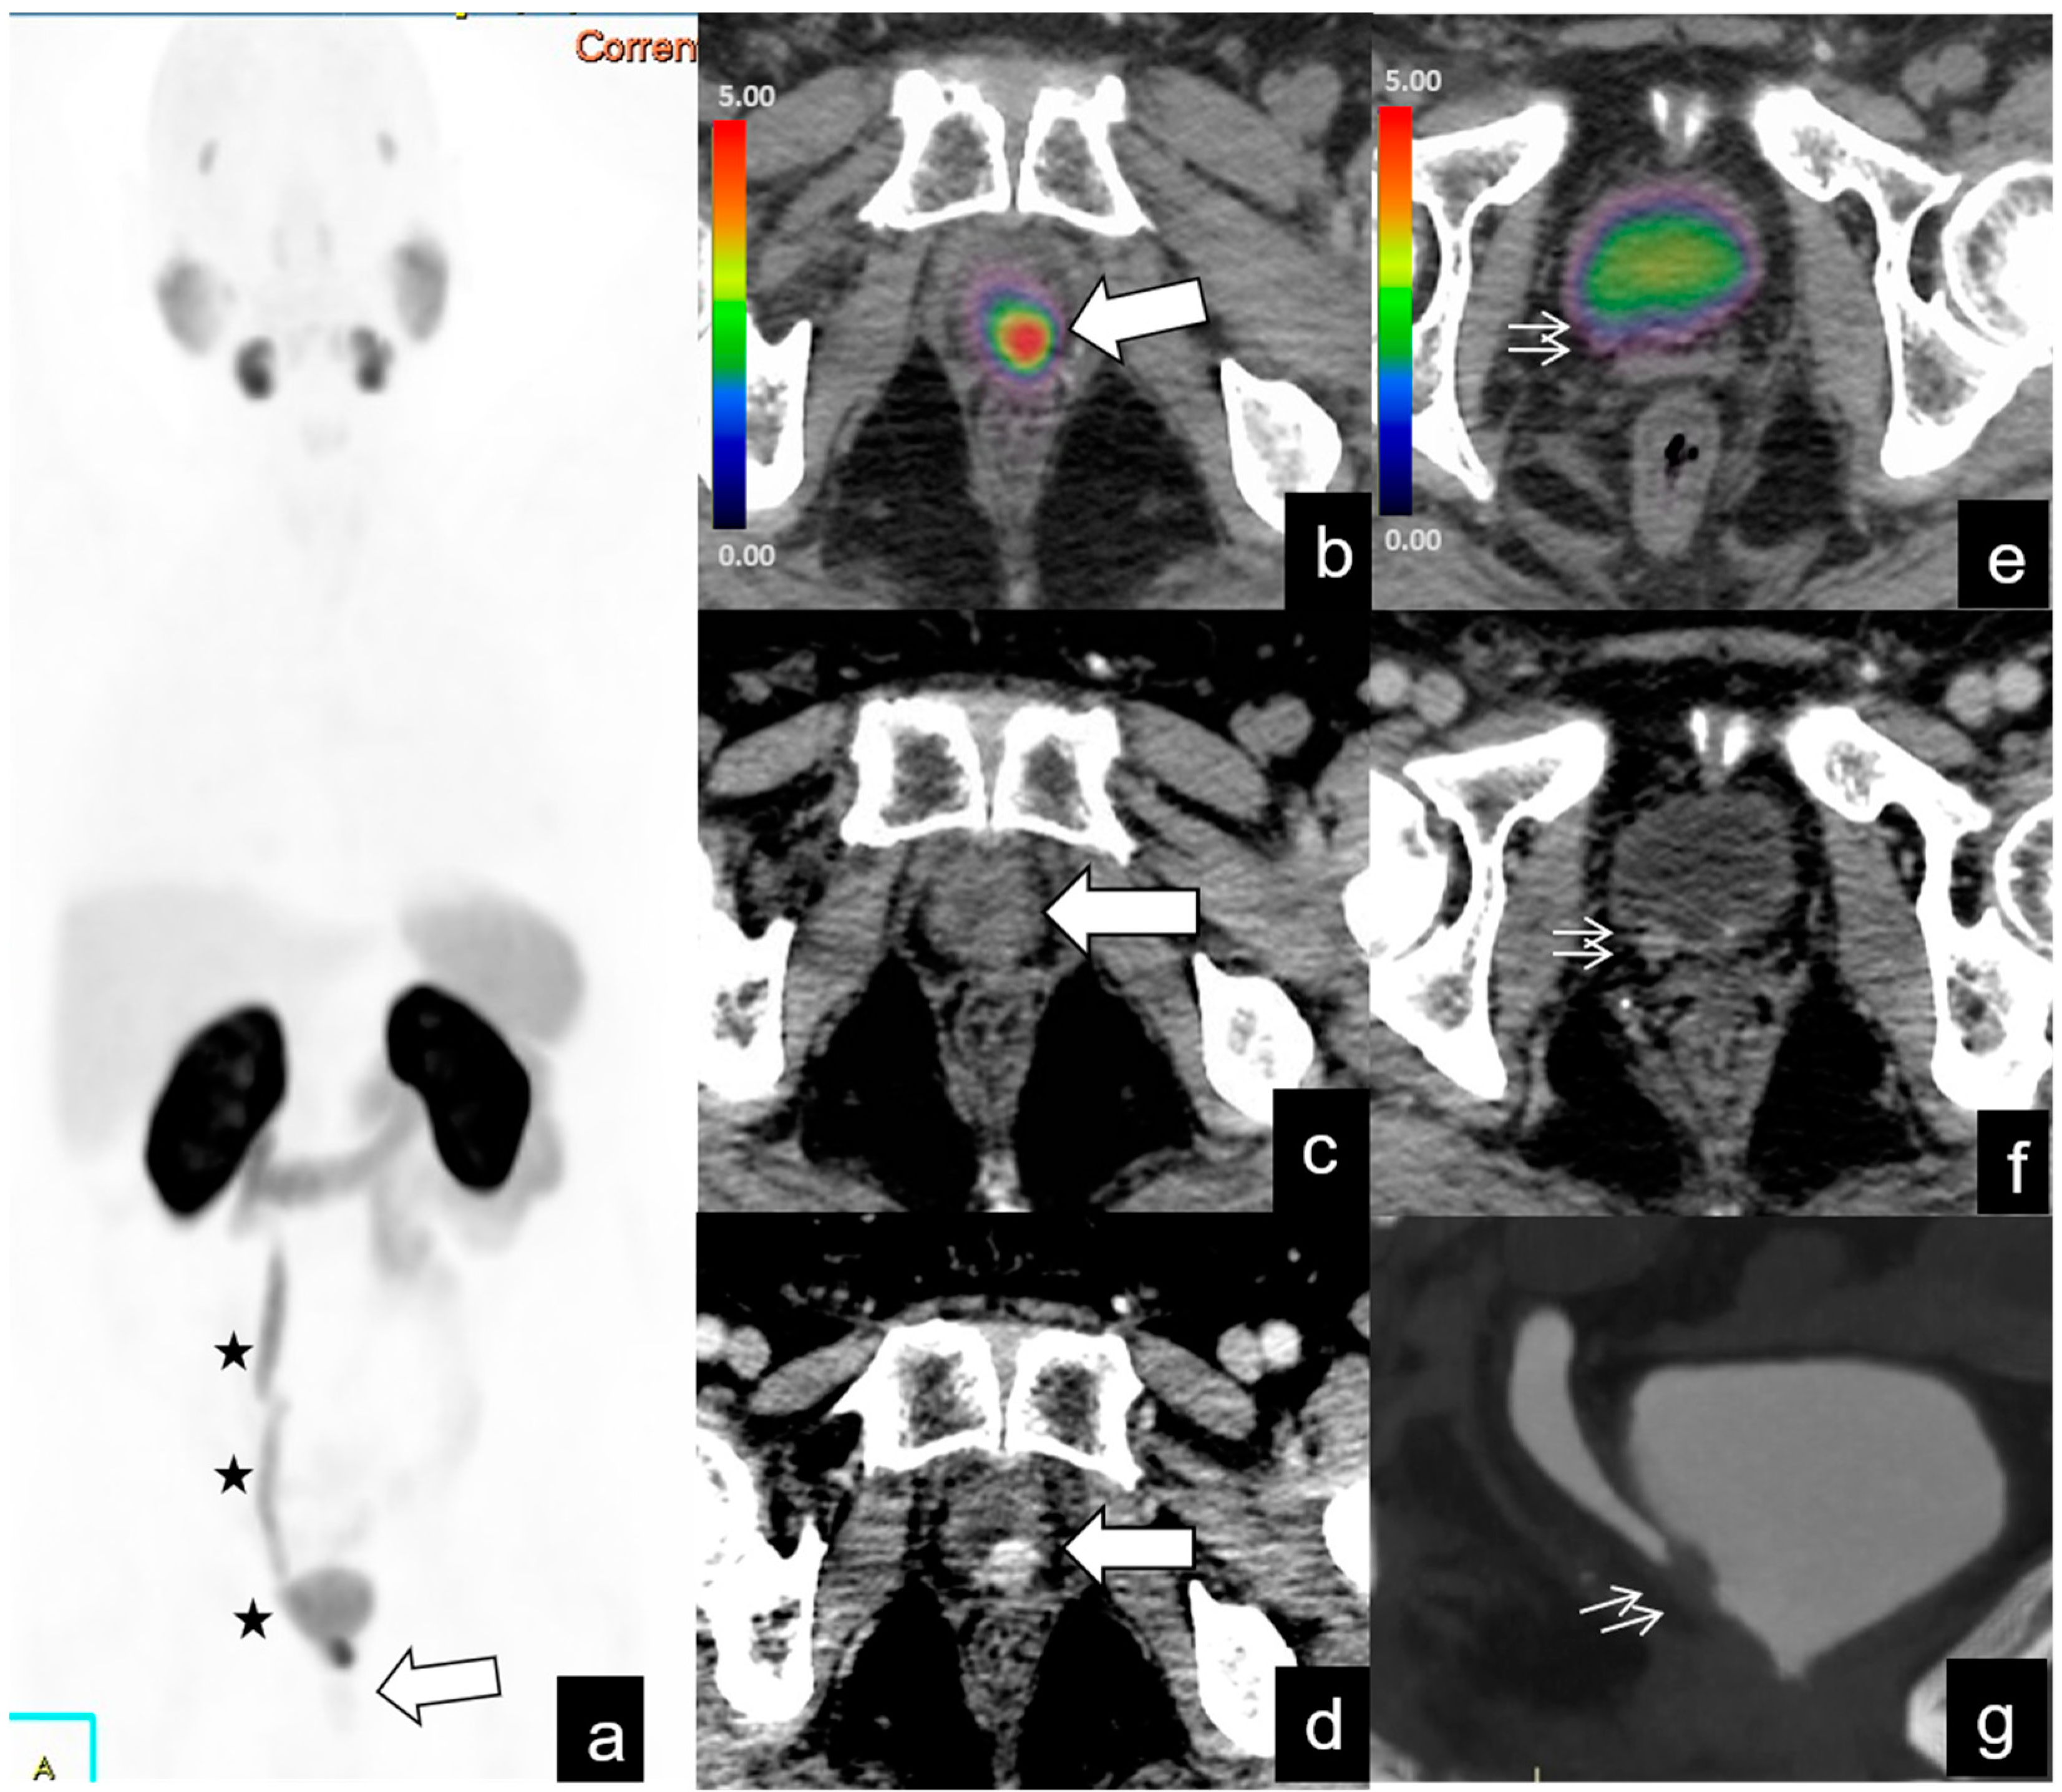

| Region | No. of Patients (%) | SUVmax Median | SUVmax Range | Size (mm) Median | Size (mm) Range |

|---|---|---|---|---|---|

| Local recurrence | 42/128 (32%) | 12 | 2.1–46 | 9.6 | 3–53 |

| Lymph-node metastases | |||||

| Abdominopelvic | 39/128 (30%) | 24 | 1–73 | 7.3 | 2–19 |

| Supradiaphragmatic | 4/128 (3%) | 27.2 | 3–60 | 18.5 | 15–22 |

| Bone metastases | 20/128 (15%) | 19 | 1.9–70 | ||

| Other (e.g., lung, liver) metastases | 5/128 (3%) | 14.6 | 2.5–17 |